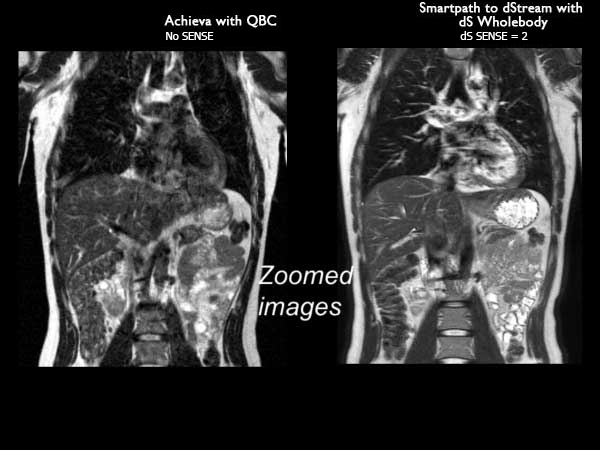

Total Body Imaging

Whole Body imaging

Used Solution

• System

• Coil

• Clinical Application